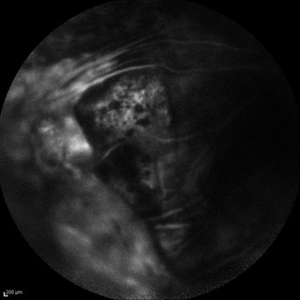

Behcet's Disease Behcet's DiseaseMar 13 2013 by Hamid Ahmadieh, MD Early phase FA of the left eye of a 23-year-old man with retinal vasculitis due to Behcet's disease . Photographer: Solmaz Shahmohammad, Negah Eye Center, Tehran Imaging device: Heidelberg Spectralis Condition/keywords: retinal vasculitis

Behcet's Disease Behcet's DiseaseMar 13 2013 by Hamid Ahmadieh, MD Mid phase FA of the left eye of a 23-year-old man with retinal vasculitis due to Behcet's disease . Photographer: Solmaz Shahmohammad , Negah Eye Center, Tehran Imaging device: Heidelberg Spectralis Condition/keywords: retinal vasculitis

Behcet's Disease Behcet's DiseaseMar 13 2013 by Hamid Ahmadieh, MD Late phase FA of the left eye of a 23-year-old man with retinal vasculitis due to Behcet's disease . Photographer: Solmaz Shahmohammad, Negah Eye Center, Tehran Imaging device: Heidelberg Spectralis Condition/keywords: retinal vasculitis

Behcet's Disease Behcet's DiseaseMar 13 2013 by Hamid Ahmadieh, MD Wide field FA of the left eye of a 23-year-old man with retinal vasculitis due to Behcet's disease . Photographer: Solmaz Shahmohammadi , Negah Eye Center, Tehran Imaging device: Heidelberg Spectralis Condition/keywords: retinal vasculitis